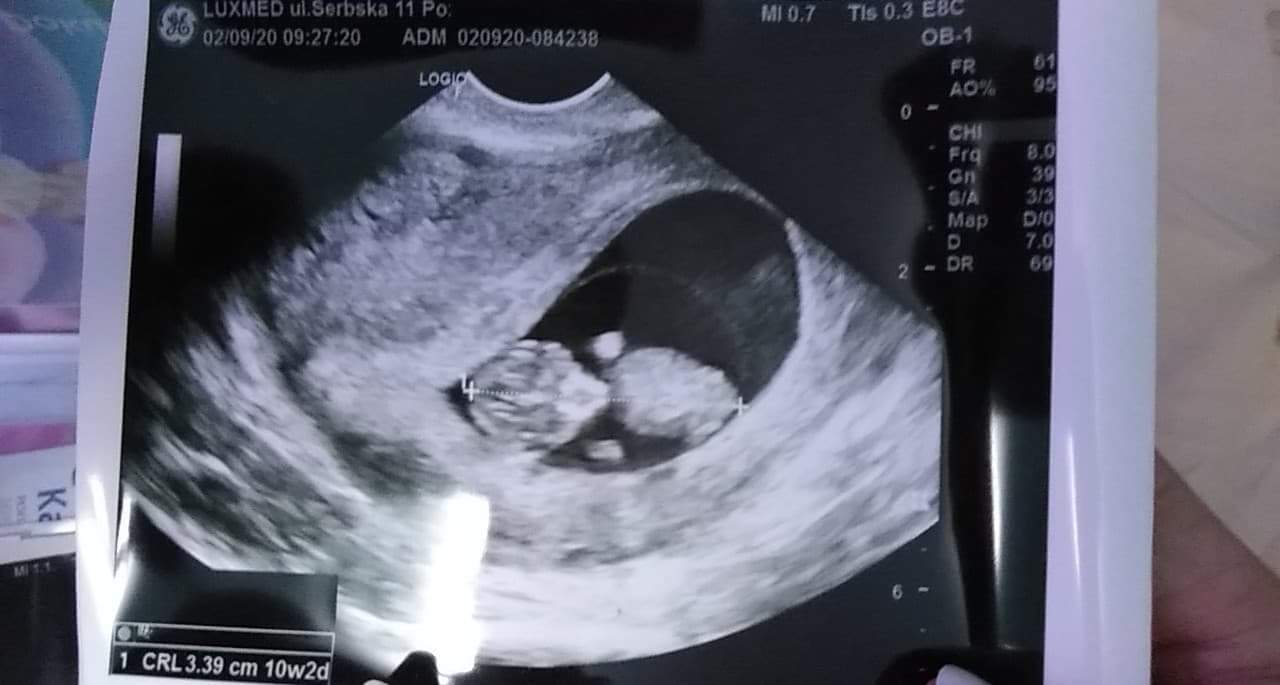

Dzisiaj byłam na wizycie kontrolnej, bo tydzień temu miałam skurcze brzucha i się trochę przestraszyłam, na wizycie okazało się, że jest ok i prawdopodobnie to zaparcia, ale kazali zrobić jeszcze jedne badanie za tydzień, więc dzisiaj poszłam i wychodzi mi z USG 10+2 😊😊😊🤗😍❤ mój szkrab ma 3,5cm, wygląda już jak dziecko, rusza fajnie rączkami i nóżkami ❤❤❤😍😆

Za 3 tygodnie prenatalne, ale dzisiaj lekarz powiedział, że na tym etapie powinno być widać płeć, a nie widać jąderek, więc duże prawdopodobieństwo, że to DZIEWCZYNKA! ❤❤❤❤😍🤗😁😊

Przesyłam zdjęcie mojej kruszynki i mojego brzucha 😱😱😱😱🙈😂😂